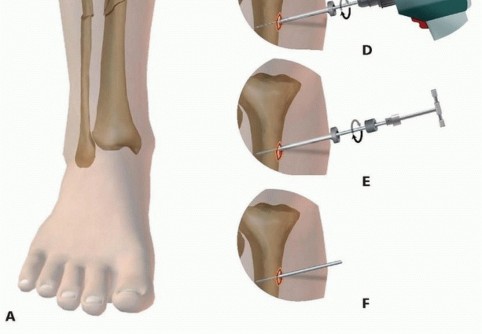

Pin Insertion Technique The correct insertion technique involves incising the skin directly at the side of pin insertion. After a generous incision is made, dissection is carried directly down to bone and the periosteum is incised where anatomically feasible ( TECH FIG 1A). A small Penfield-type elevator is used to gently reflect the periosteum off the bone at the site of insertion ( TECH FIG 1B). Extraneous soft tissue tethering and necrosis is avoided by minimizing soft tissue at the site of insertion.

### TECH FIG 1 • Proper pin insertion technique. A. A generous incision is made over the location of the pin site. B. A small elevator is used to elevate all soft tissues, including the periosteum, off the bone to help avoid the tethering of excessive soft tissues during predrilling and pin insertion. C. A trocar is advanced to bone to protect the soft tissues. D. The pin site is predrilled through the trocar to avoid incarcerating and tethering soft tissues. E,F. A T-handle insertion chuck is used to hand-torque the pin into position, achieving purchase in both the near and far cortices.

A trocar and drill sleeve are advanced directly to bone, minimizing the amount of soft tissue entrapment that might be encountered during predrilling ( TECH FIG 1C,D). A sleeve should also be used if a self-drilling pin is selected. After predrilling, an appropriate-size depth of pin is advanced by hand to achieve bicortical purchase. Any offending soft tissue tethering should be released with a small scalpel ( TECH FIG 1E,F). Fluoroscopy is used to ensure that transcortical pin placement is avoided ( TECH FIG 1G). 537

- TECH FIG 1 • (continued) G. It is important to place the trocar over the center of the medullary canal and confirm its location to ensure that the pin captures the near cortex, medullary canal, and far cortex. This confirms that a transcortical pin is avoided, as these pins can be stress risers and may lead to pin-related fracture or pin infection due to the drilling and placement in only hard, dense cortical bone.